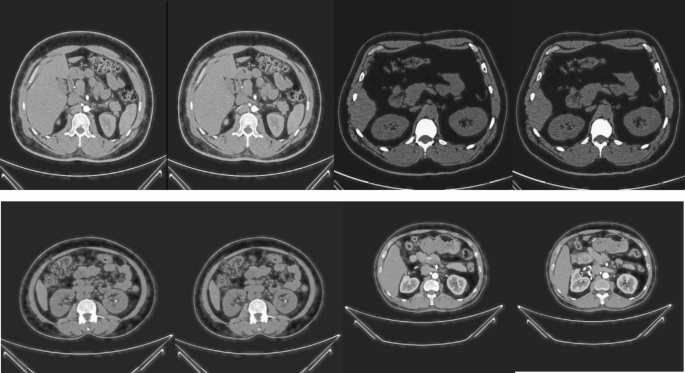

Figure 5 shows samples of the original images, and Fig. 6 illustrates samples of the enhanced images. These images clearly illustrate the improvements in image quality and details achieved by applying the MSF technique.

Samples of the enhanced images.